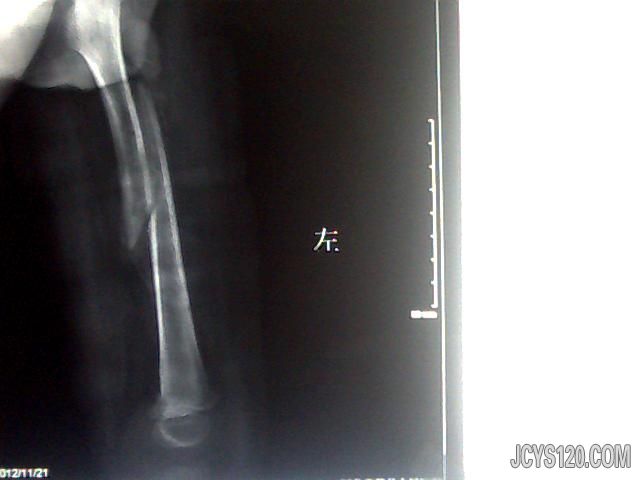

• 看看这个股骨头 attach_img agree  ...2

• 真人无奈 2013-7-2

• 女。26岁,有外伤史,5年前从楼梯上摔倒。现走路无跛行,下肢内收,外旋时轻度受限,无疼痛。大家看看,现在的病情状况,怎样治疗为妥。  阅读全文>